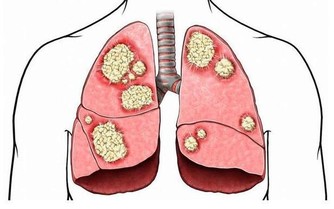

“風邪”是屬於六邪之一,常說“風為百病之長”,若是傳染病暴發流行的風邪則稱為“疫氣”或“癘氣”,也就是現在所講的病毒、立克次體和細菌等病原微生物。而我們都知道春季恰恰就是傳染病的高發期,所以老人說“春捂秋凍”不是沒有原因的,春季往往氣溫溫差大,因此要高血壓患者朋友們應當注意保暖。